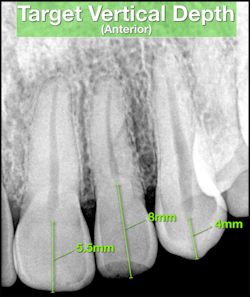

Before initiating treatment, an estimate can be made from the tooth’s occlusal surface (or incisal edge) to various levels within the tooth. This estimate represents a “target vertical depth” and can assist with endodontic access when measured to the roof of the pulp chamber (Fig. 1). In multi-rooted teeth, an additional “terminal depth estimate,” measured to the furcation, could help avoid iatrogenic perforation (Fig 2).

A bitewing radiograph is considered to be the most spatially accurate and dimensionally stable image with respect to 2-dimensional radiography, making it ideal to estimate the depth when treating posterior teeth. Estimates for anterior teeth must be determined from the slightly more distorted periapical radiograph (Fig 3). This visual exercise can also influence case selection.